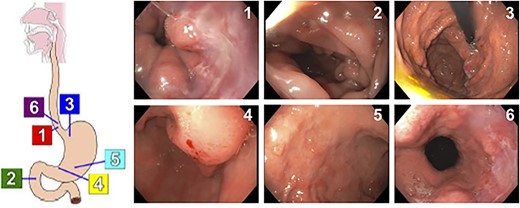

A 61-year-old woman presented to the emergency department with acute onset abdominal pain, nausea and non-bilious emesis. Her medical history was significant for rheumatoid arthritis, hypertension, chronic kidney disease and long-term heroin abuse. Physical examination was significant for mild epigastric tenderness with no peritoneal signs, and lab work was unremarkable at this time. Given her symptoms and extensive medical history, the patient underwent an esophagogastroduodenoscopy (EGD). The distal esophagus appeared red and macerated as a result of recent vomiting, and we observed dispersed, multiple 3-mm non-bleeding erosions in the gastric antrum with no stigmata of recent bleeding (Fig. 1). Gastric biopsies revealed a poorly differentiated, GATA3 positive, CDX2 negative signet ring carcinoma (Fig. 2). The patient was referred to medical oncology, but was lost to follow up.

Results of EGD showing dispersed, 3-mm non-bleeding erosions in the gastric antrum.